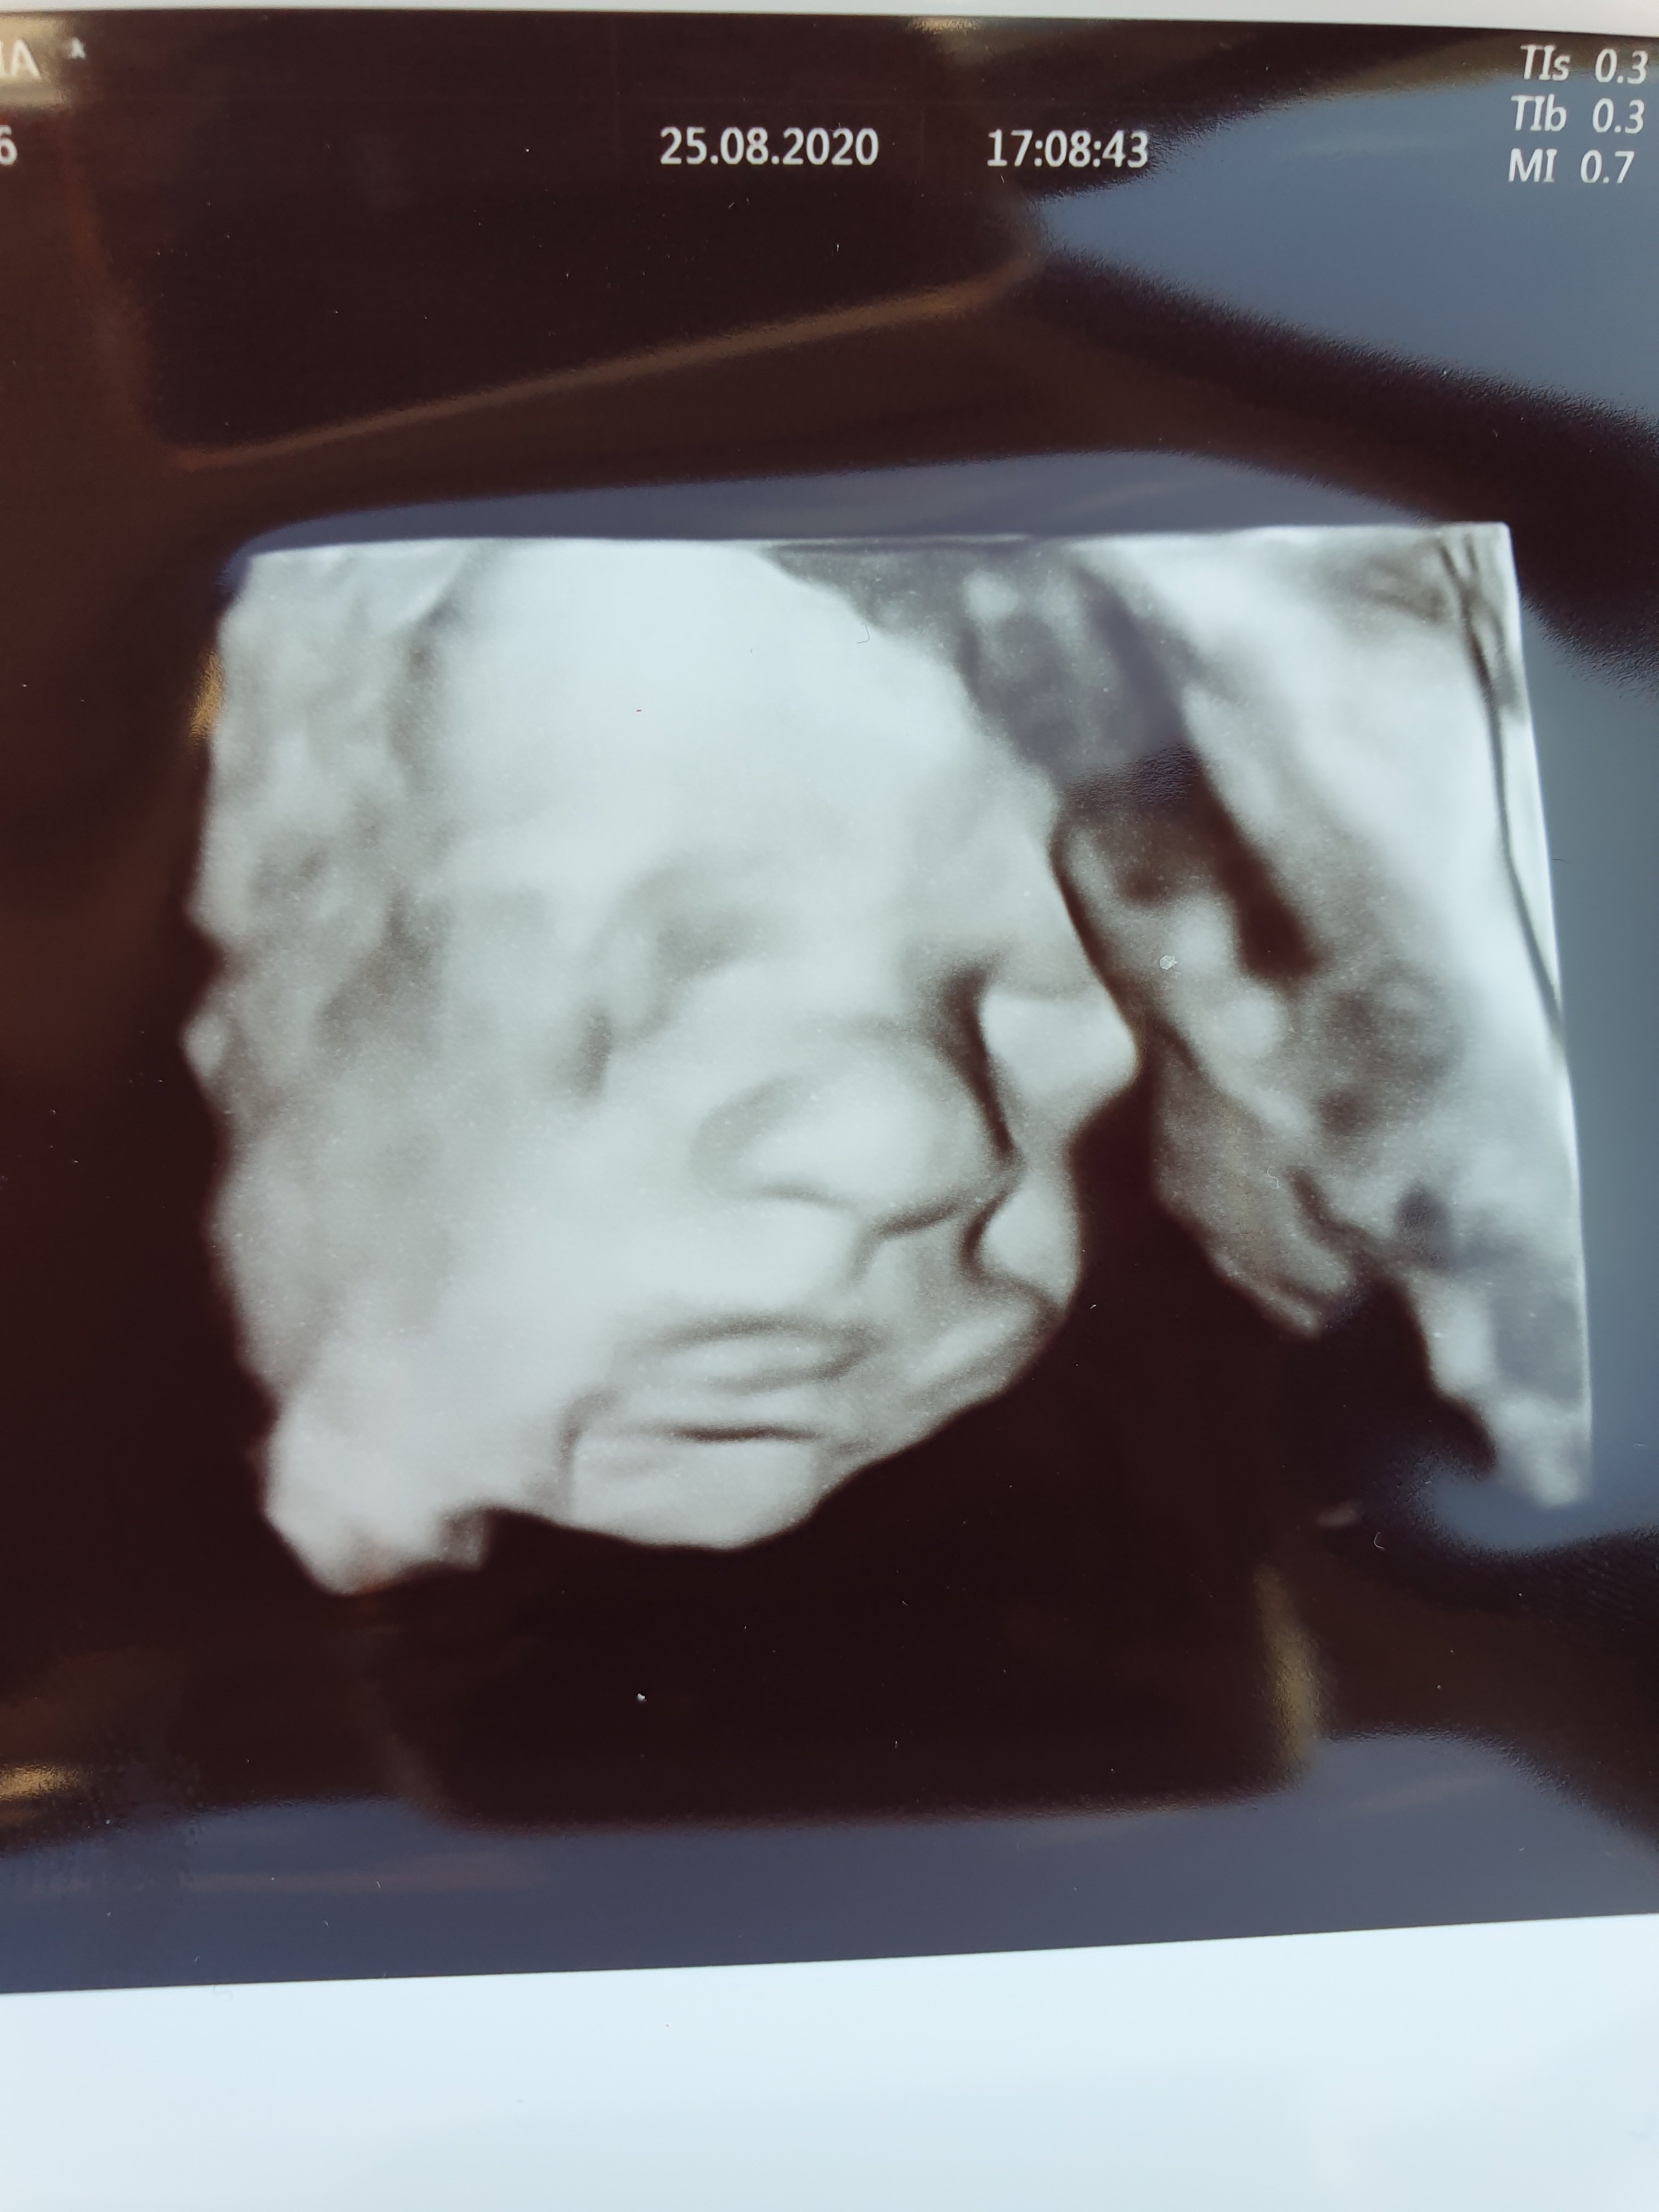

Bylam na USG III trymestru, na dzien 30+4 młody ważył 1650 g i wszystko w porzadku.